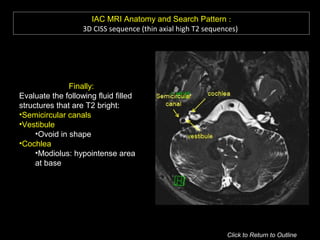

IAC MRI Anatomy and Search Pattern :

3D CISS sequence (thin axial high T2 sequences)

Review axial images superior to inferior

Look at CN V and Meckel’s cave Look at Petrous Apex

Finally:

Evaluate the following fluid filled

structures that are T2 bright:

•Semicircular canals

•Vestibule

•Ovoid in shape

•Cochlea

•Modiolus: hypointense area

at base

Click to Return to Outline